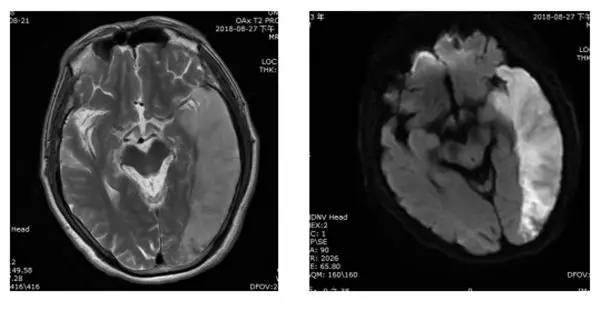

早期脑梗患者